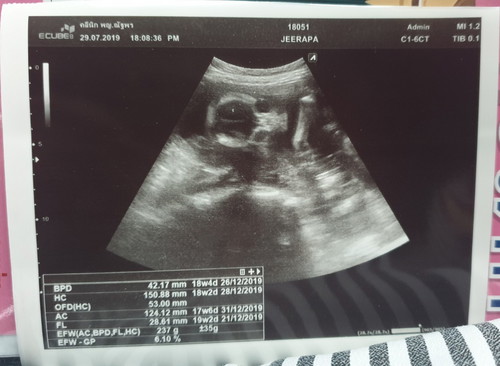

19 weeks 2 days

นน. 237 กรัม คุณหมอบอกว่า เบบี้เกิร์ล 80%+ ให้ดูเองดูยังไงก็ดูไม่ออกค่ะ ?

VIP Parentsนน. 237 กรัม คุณหมอบอกว่า เบบี้เกิร์ล 80%+ ให้ดูเองดูยังไงก็ดูไม่ออกค่ะ ?